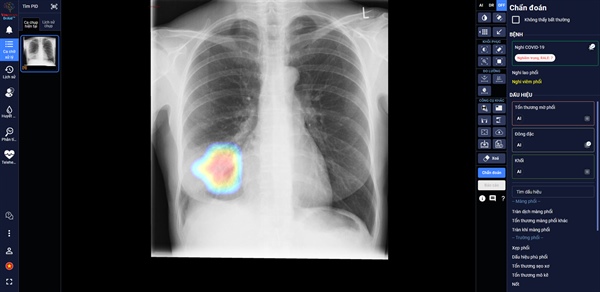

DrAid giúp bác sĩ theo dõi mức độ tổn thương phổi ở một bệnh nhân F0 trên ảnh X-quang phổi

Trong các bệnh viện thu dung điều trị Covid-19, DrAid cho Covid-19 giúp các bác sĩ đánh giá mức độ tổn thương phổi của bệnh nhân Covid-19 qua các ngày, từ đó đưa ra các chỉ định điều trị kịp thời và hiệu quả cho bệnh nhân.